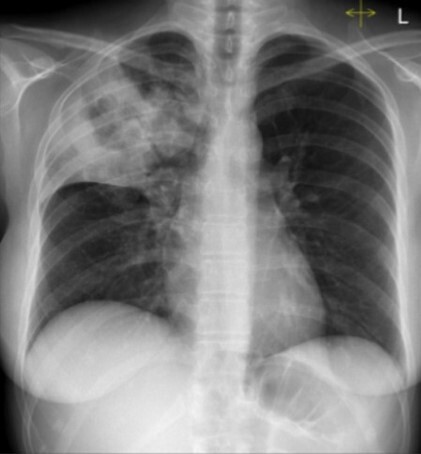

Q

A

Fevers, productive cough and hemoptysis. Recent intravenous drug use. No history of travel or exposure to tuberculosis.

Right middle lobe consolidation with an associated cavitating lesion.

Community acquired methicillin resistant staphylococcus aureus pneumonia